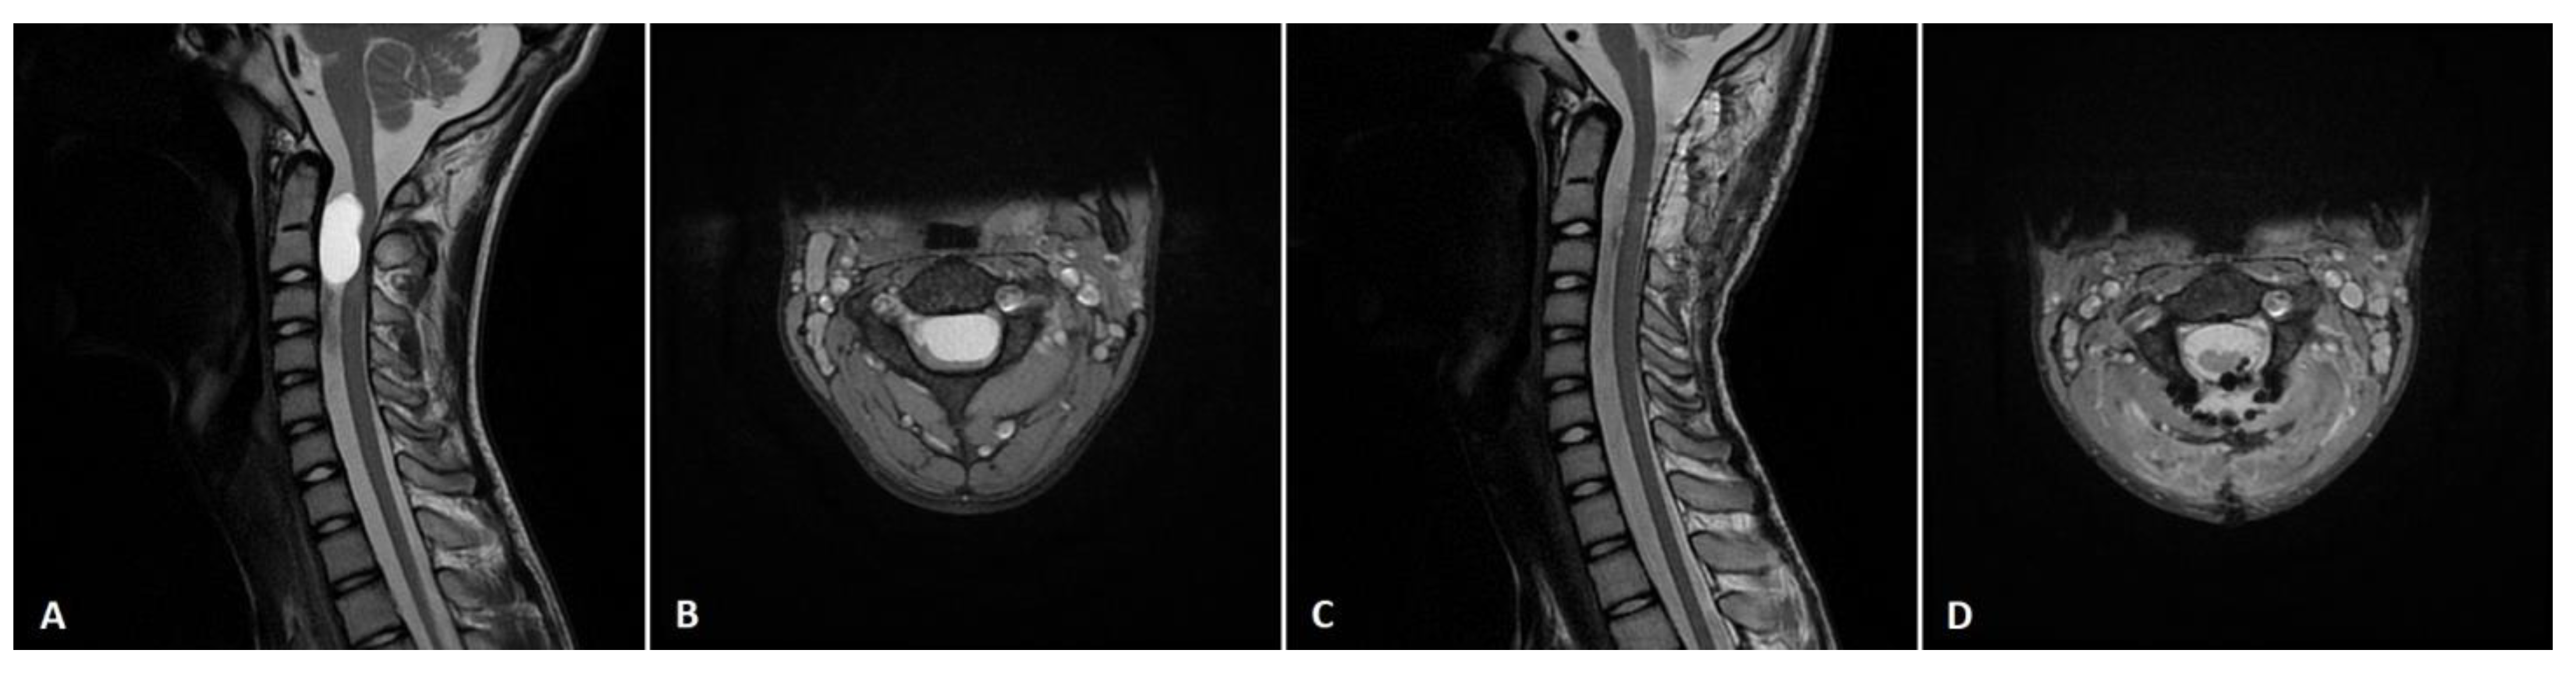

| 5 | F | 5 | 4 | Motor | C4-C7, anterolateral | Rhabdoid meningioma | YES | 5 | Motor |

| 12 | M | 7 | 3 | Sensory, motor | C5-T4, posterolateral | Anaplastic ependymoma | YES | 4 | Motor |